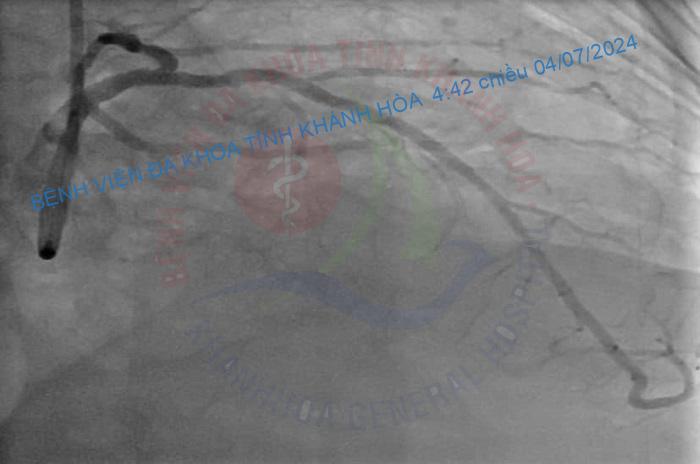

Kỹ thuật can thiệp động mạch vành qua da bằng phương pháp DK – Crush trong can thiệp tổn thương chia đôi là một kỹ thuật khó, chỉ được thực hiện ở các trung tâm tim mạch can thiệp lớn có các bác sỹ giàu kinh nghiệm. Từ hơn 3 năm nay, Khoa Tim mạch Can thiệp Bệnh viện Đa khoa tỉnh Khánh Hòa đã tiến hành kỹ thuật này một cách thường quy, có tỷ lệ thành công cao, hiệu quả và an toàn cho người bệnh./.